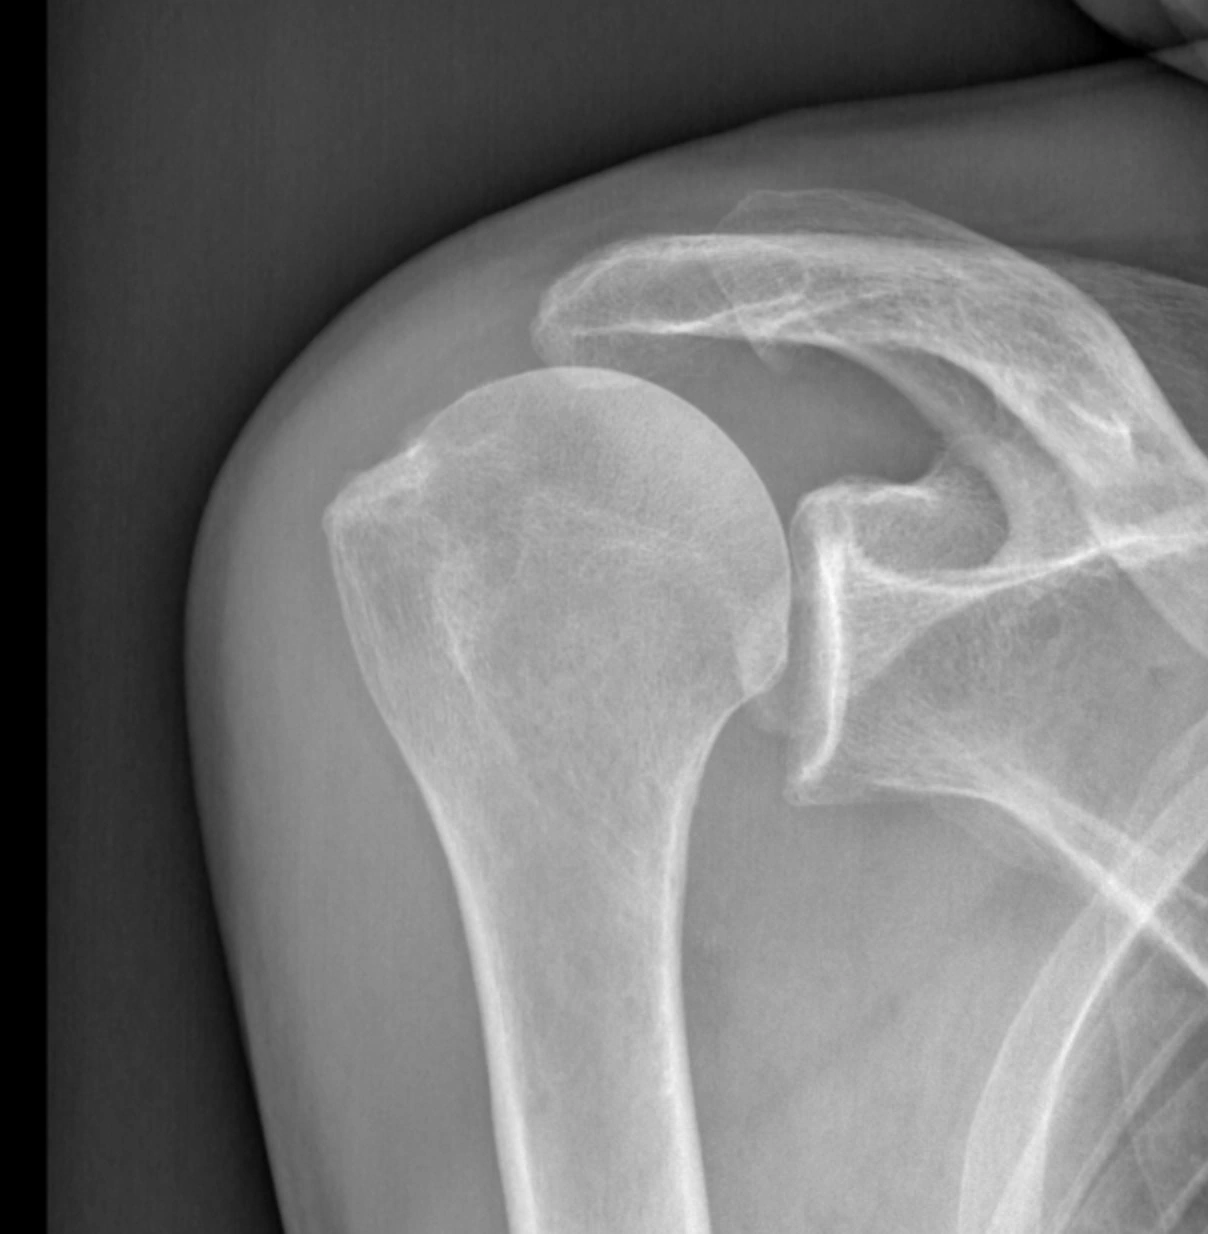

Cliniquement, on retrouve un enraidissement progressif plus ou moins douloureux de l’épaule qui peut s’associer à des blocages articulaires. Le diagnostic est radiologique avec un pincement de l’interligne articulaire, une déformation de la tête humérale, une condensation de l’os, la présence d’ostéophytes ou parfois des fragments libres dans l’articulation (ostéochondromes).

arthrose épaule

radio arthrose de l'épaule

radio arthrose épaule